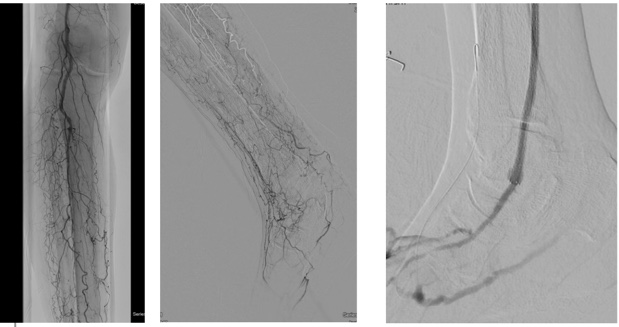

As in many cases, the patient presented with a relatively small (0.5cm x 0.5cm x 0.2cm) DFU under the first metatarsal on the right foot (Figure 1a, b). Over 2 months, the DFU did not close, instead, it grew with increasing depth to 0.4cm and developed osseous involvement. On her second hospitalization there was concern of DFU infection, and she underwent vascular imaging to assess the extent of her peripheral arterial disease (PAD). Her ankle brachial indices (ABIs) were falsely elevated due to her comorbidities and toe pressure was less than 40mmHg (Figure 2). Duplex ultrasound showed significant mural calcification of the tibial arteries of the right calf with occlusion of the right posterior tibial artery in the proximal calf and the right anterior tibial and peroneal arteries in the distal calf. Angiogram demonstrated severe tibial disease not amenable to endovascular interventions with no bypass target available (Figure 3). As described in the article by Montero-Baker and colleagues,10 given her occluded anterior tibial artery and suitable great saphenous vein, she underwent a hybrid superficial venous arterialization for limb salvage (Figure 4).